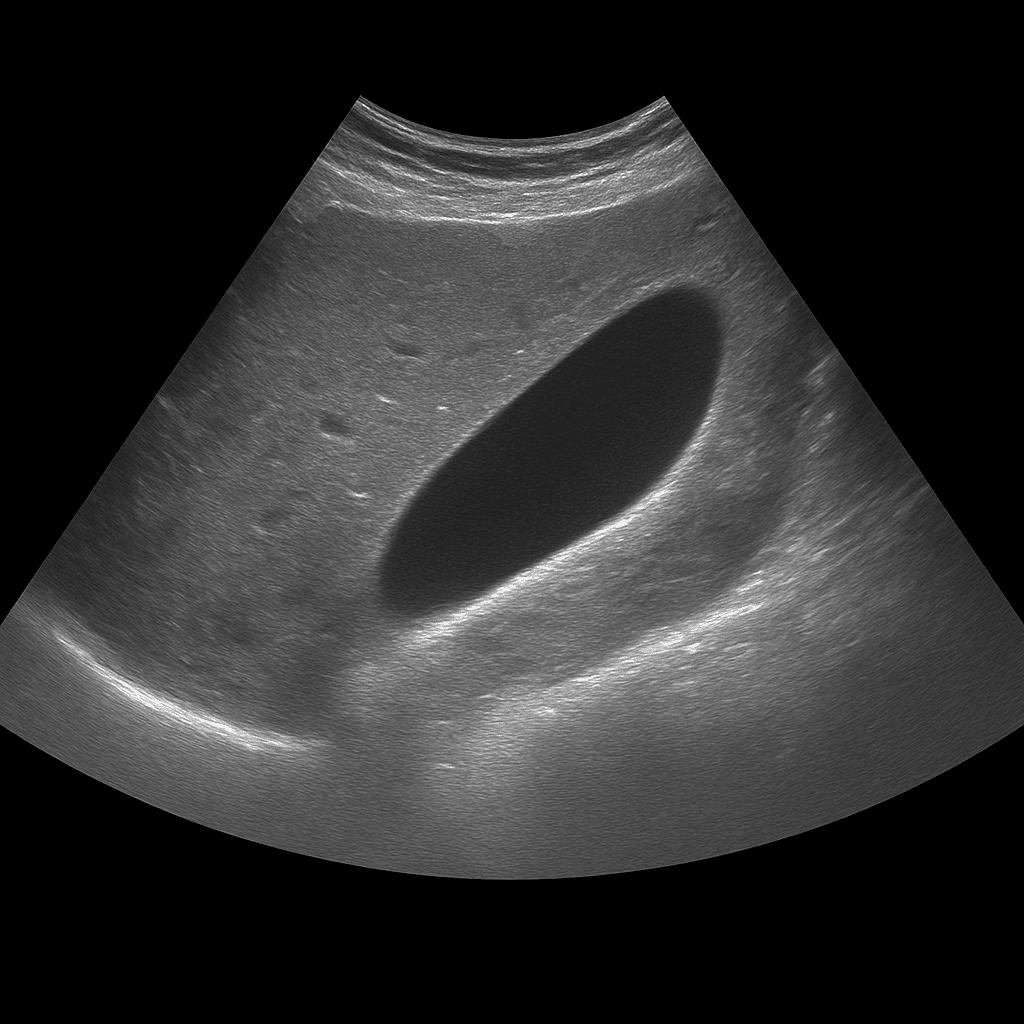

A gallbladder ultrasound is used to examine the gallbladder wall, contents and function. The examination is performed by a specialist in radiology and provides detailed real-time images that show whether the gallbladder contains stones, fluid or signs of inflammation. Gallbladder ultrasound is used as the first-line method when gallstone disease or inflammation of the gallbladder (cholecystitis) is suspected.

A gallbladder ultrasound is recommended for pain under the right rib cage, nausea, bloating or recurrent discomfort after eating fatty foods. The examination can show whether the gallbladder contains stones, sludge (biliary gravel) or a thickened wall that indicates inflammation. It is also used to follow up on previous gallstone problems or after surgery where parts of the biliary system remain.

The examination is performed while you lie on your back or slightly on your left side. A gel is applied to the skin and the doctor moves the ultrasound probe over the area under the right rib cage. The examination usually takes 10–20 minutes. For the best image quality, you need to fast for at least 4–6 hours beforehand, as an empty gallbladder is difficult to assess.